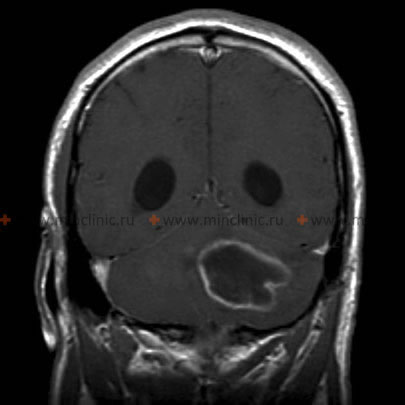

მაგნიტურ-რეზონანსული ტომოგრაფია ტარდება თავის ტვინის აბსცესის ეჭვზე.

- მრტ არის სასურველი გამოსახულების მეთოდი ტვინის აბსცესების დიაგნოსტიკისთვის.

CT და MRI ტომოგრაფია |

ნაკლებად გამიჯნული ანთება | CT: სქელი რგოლის ფორმის გამოკვეთა MRI: T1 ჰიპოინტენსიური, T2 ჰიპერინტენსიური |

გარსს შემოვლებული ნეოვასკულარული რეტიკულარული ქსელი | CT: თხელი რგოლის ფორმის გამოკვეთა MRI: T1 ჰიპოინტენსიური — შეშუპება/ცენტრი, ჰიპერინტენსიური — კაფსულა, T2 ჰიპერინტენსიური — შეშუპება, კაფსულა და ცენტრალურად შეზღუდული დიფუზია |